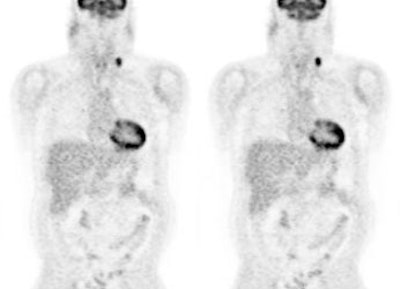

Monitor response to therapy in lymphoma: The patient shown below was a 29 year old male with a history of recurrent lymphoma despite chemotherapy and stem cell transplant. The patients initial PET scan (left) demonstrated extensive nodal disease throughtout the neck, chest, abdomen, and pelvis. The patient was treated with a repeat stem cell transplant. A post-treatment FDG PET exam demonstrated interval resolution of previously identified sites of disease consistent with a response to therapy. Note renal collecting system activity on both studies. The exams were performed on a Siemens ECAT EXACT PET scanner (manufactured by CTI). Case courtesy of North Texas Clinical PET Institute, Dallas, Texas and CTI PET Systems, Inc. Click images to view cine avi file (230K) |

|

Monitor response to therapy in lymphoma: The patient shown below is a teenage male with Hodgkins disease. The pre-therapy scan confirmed disease only above the diaphragm. The post-therapy scan was performed following two cycles of chemotherapy and demonstrated complete resolution of all sites of disease. Early data indicates that following effective chemotherapy, there is a rapid decrease in metabolic activity within the tumor. Click images to view rotating avi files (note para-cardiac and costophrenic angle nodes can also be seen on these images). |